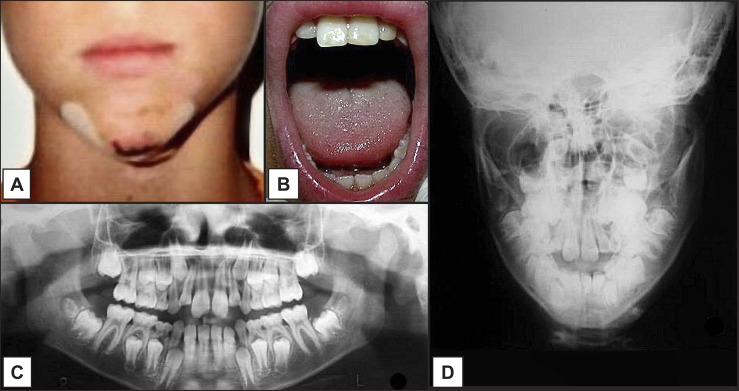

Background: Mandibular condylar fractures commonly occur after trauma and account for 25 to 35% of all mandibular fractures; its appropriate therapy still remains a point of controversy in children. The purpose of this paper is to describe the treatment of an 11-years-old male patient affected by neck-condylar fracture as result of trauma in evolutive age.

Methods: No surgical treatment was performed. A functional therapy was applied with a jaw splint. A closed treatment for mandibular condyle fractures was preferred because the amount of condylar displacement wasn't considerable.

Results: The early treatment with functional therapy generated a functional adaptation of the condyle in the glenoid fossa and a normal mandibular function. After a 12-month follow-up the fracture resolution and an optimal condylar position were recorded.

Conclusions: The current case report and literature review showed that non-surgical therapy of neck-condylar fracture in a child with lower resin splint can restore mandibular movements and aesthetics. Facial growth after one year treatment resulted normal. A conservative treatment may be appropriate for children in selected cases with minimally displaced condyle.